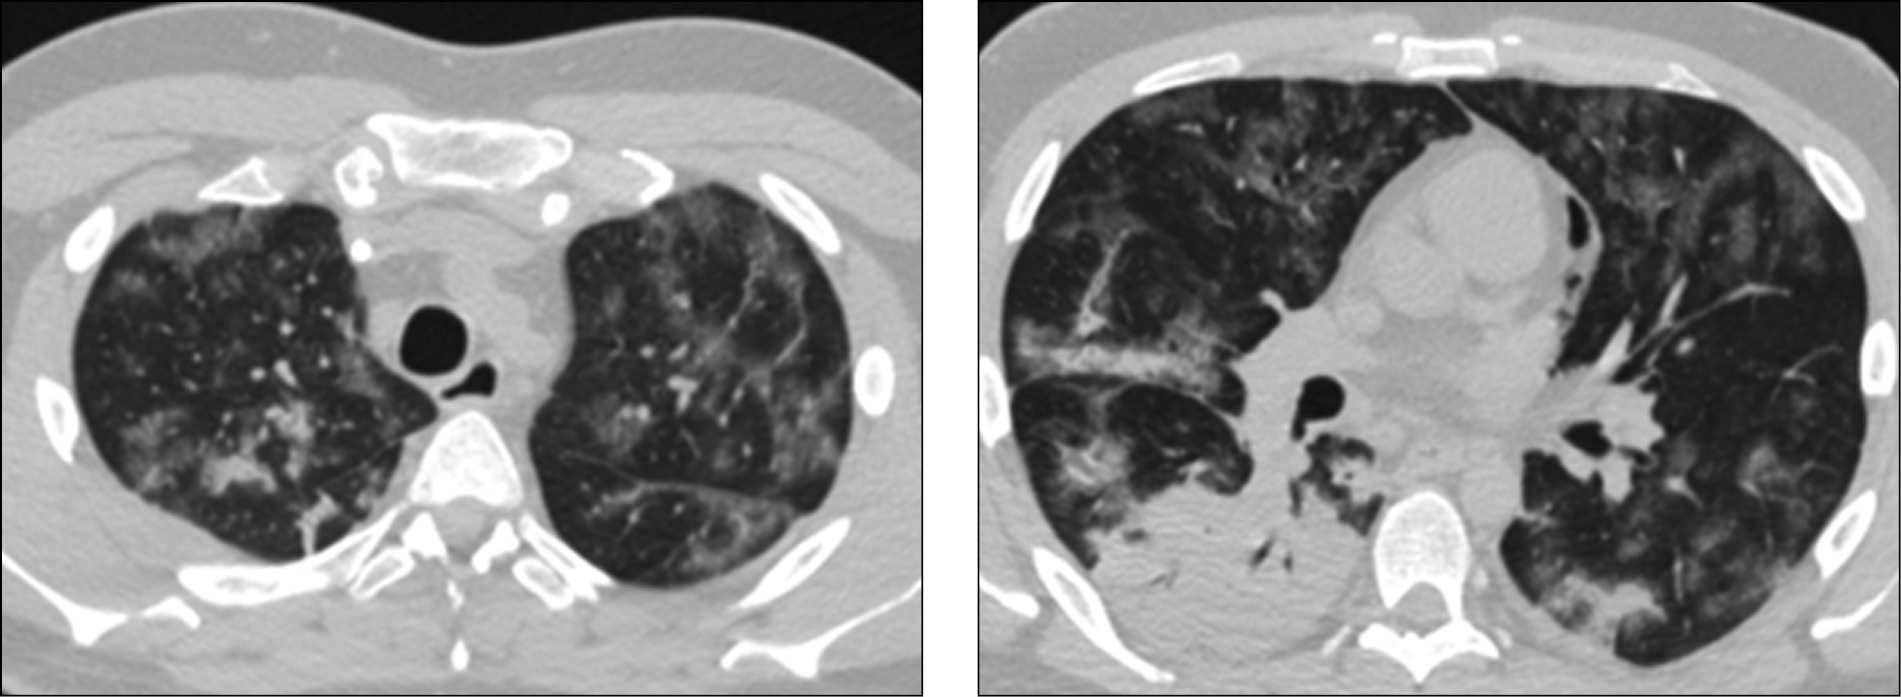

24.04.2020 повторно выполнена КТ легких: отрицательная динамика по сравнению с предыдущим исследованием, выражающаяся увеличением распространенности и интенсивности патологических изменений в легких, с субтотальным поражением легочной паренхимы, КТ4. КТ-картина позволяла предположить развитие острого респираторного дистресс-синдрома на фоне воспалительного процесса (рис. 1).

Рис. 1. Компьютерная томография легких от 24.04.2020: увеличение распространенности и интенсивности патологических изменений с субтотальным поражением легочной паренхимы, КТ4